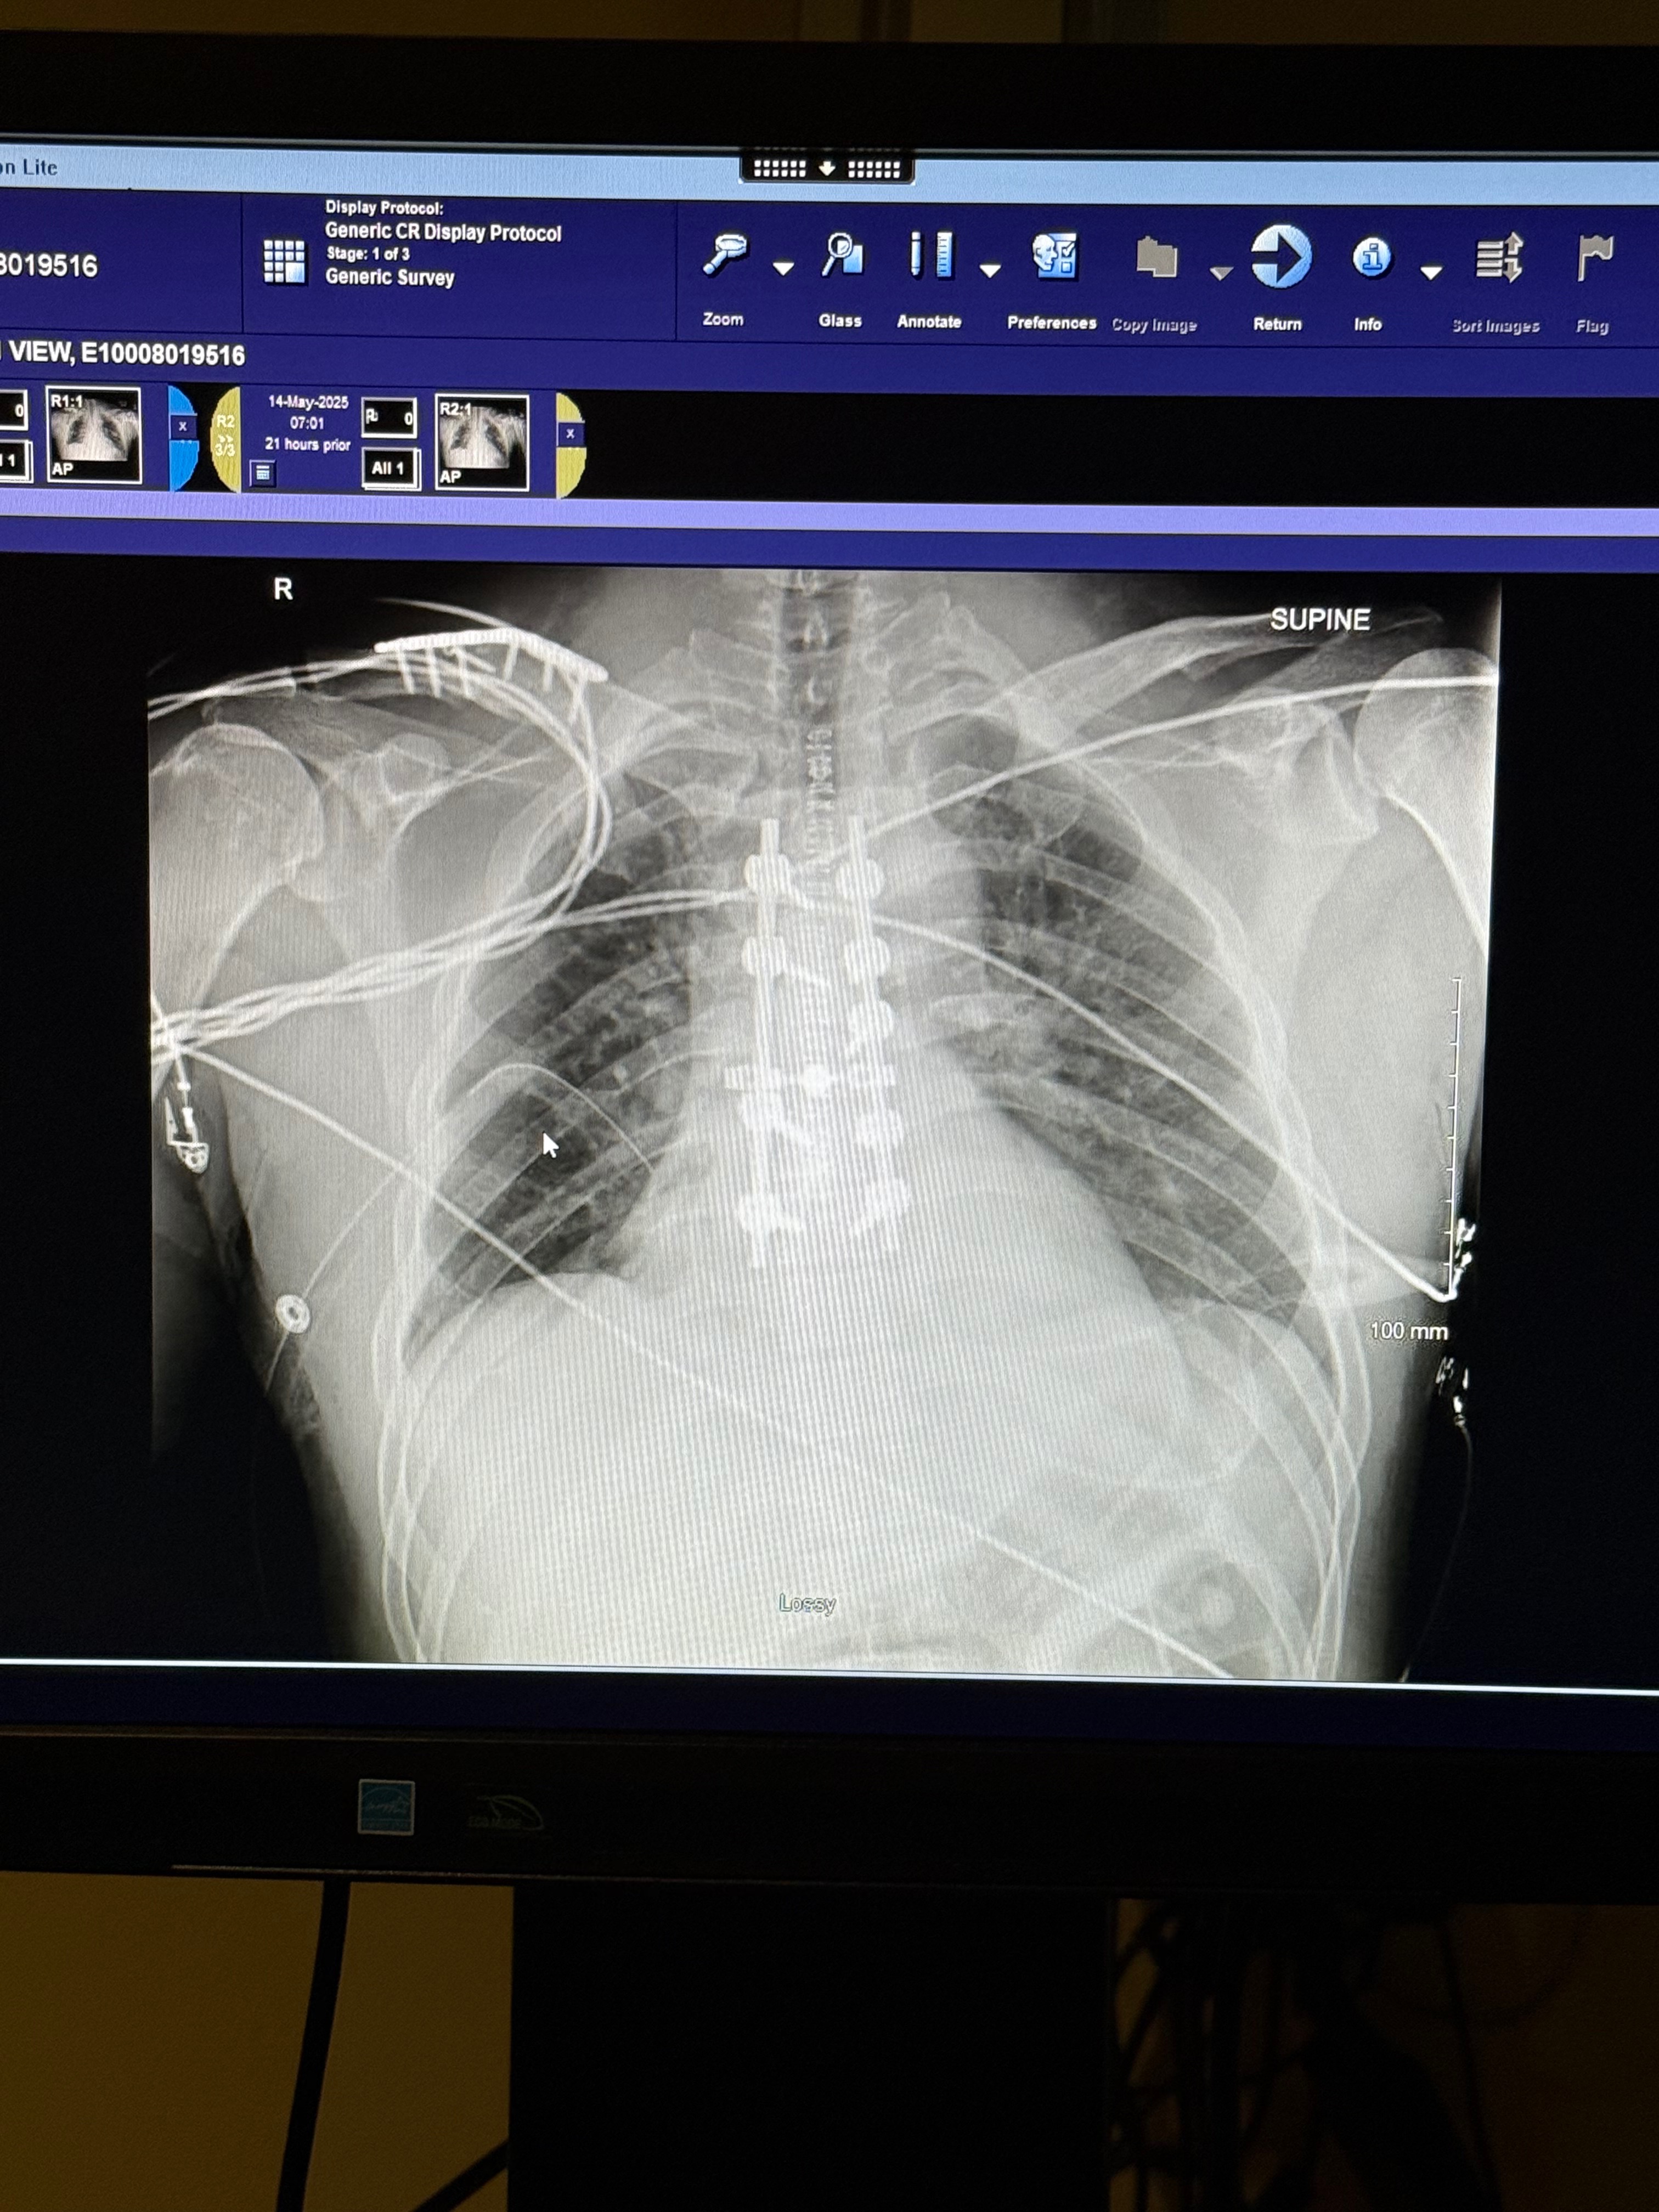

Our buddy who loves his spend his winters on the mountain is now facing a mountain of medical bills and the sort. ND had an accident on Mothers Day and broke his T-6 and had to undergo surgery to fuse his T-4 through T-8. He faces a long recovery and we can help ease the burden financially.